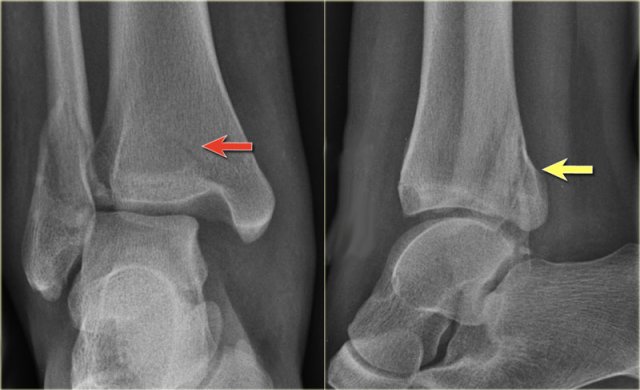

Stage 4

Finally the posterior syndesmotic ligament ruptures, or there is an avulsion of the posterior malleolus, also known as posterior malleolus fracture (red arrow).

The medial clear space is only slightly widened, but based on the stages of Lauge Hansen there must be a collateral band rupture.